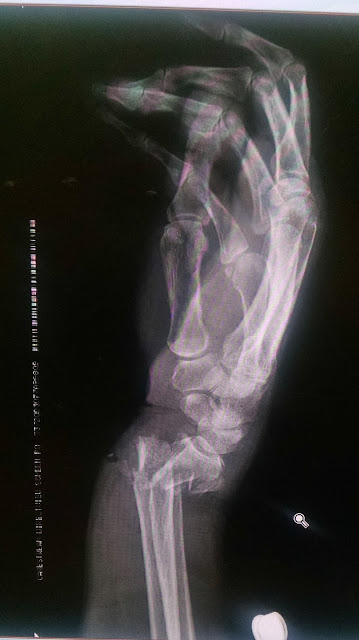

Estudios de Gabinete:

- MIELOPATIA NEOPLASICA SECUNDARIA A TUMOR VERTEBRAL METASTASICO CON LESION VERTEBRAL LITICA DE T5-T7.